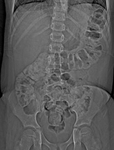

Radiografia abdominal de neonato com padrão fecal anormal e constipação. Os cólons transverso e descendente dilatados são sugestivos de doença de Hirschsprung

Do acervo de Dr. KuoJen Tsao; usado com permissão